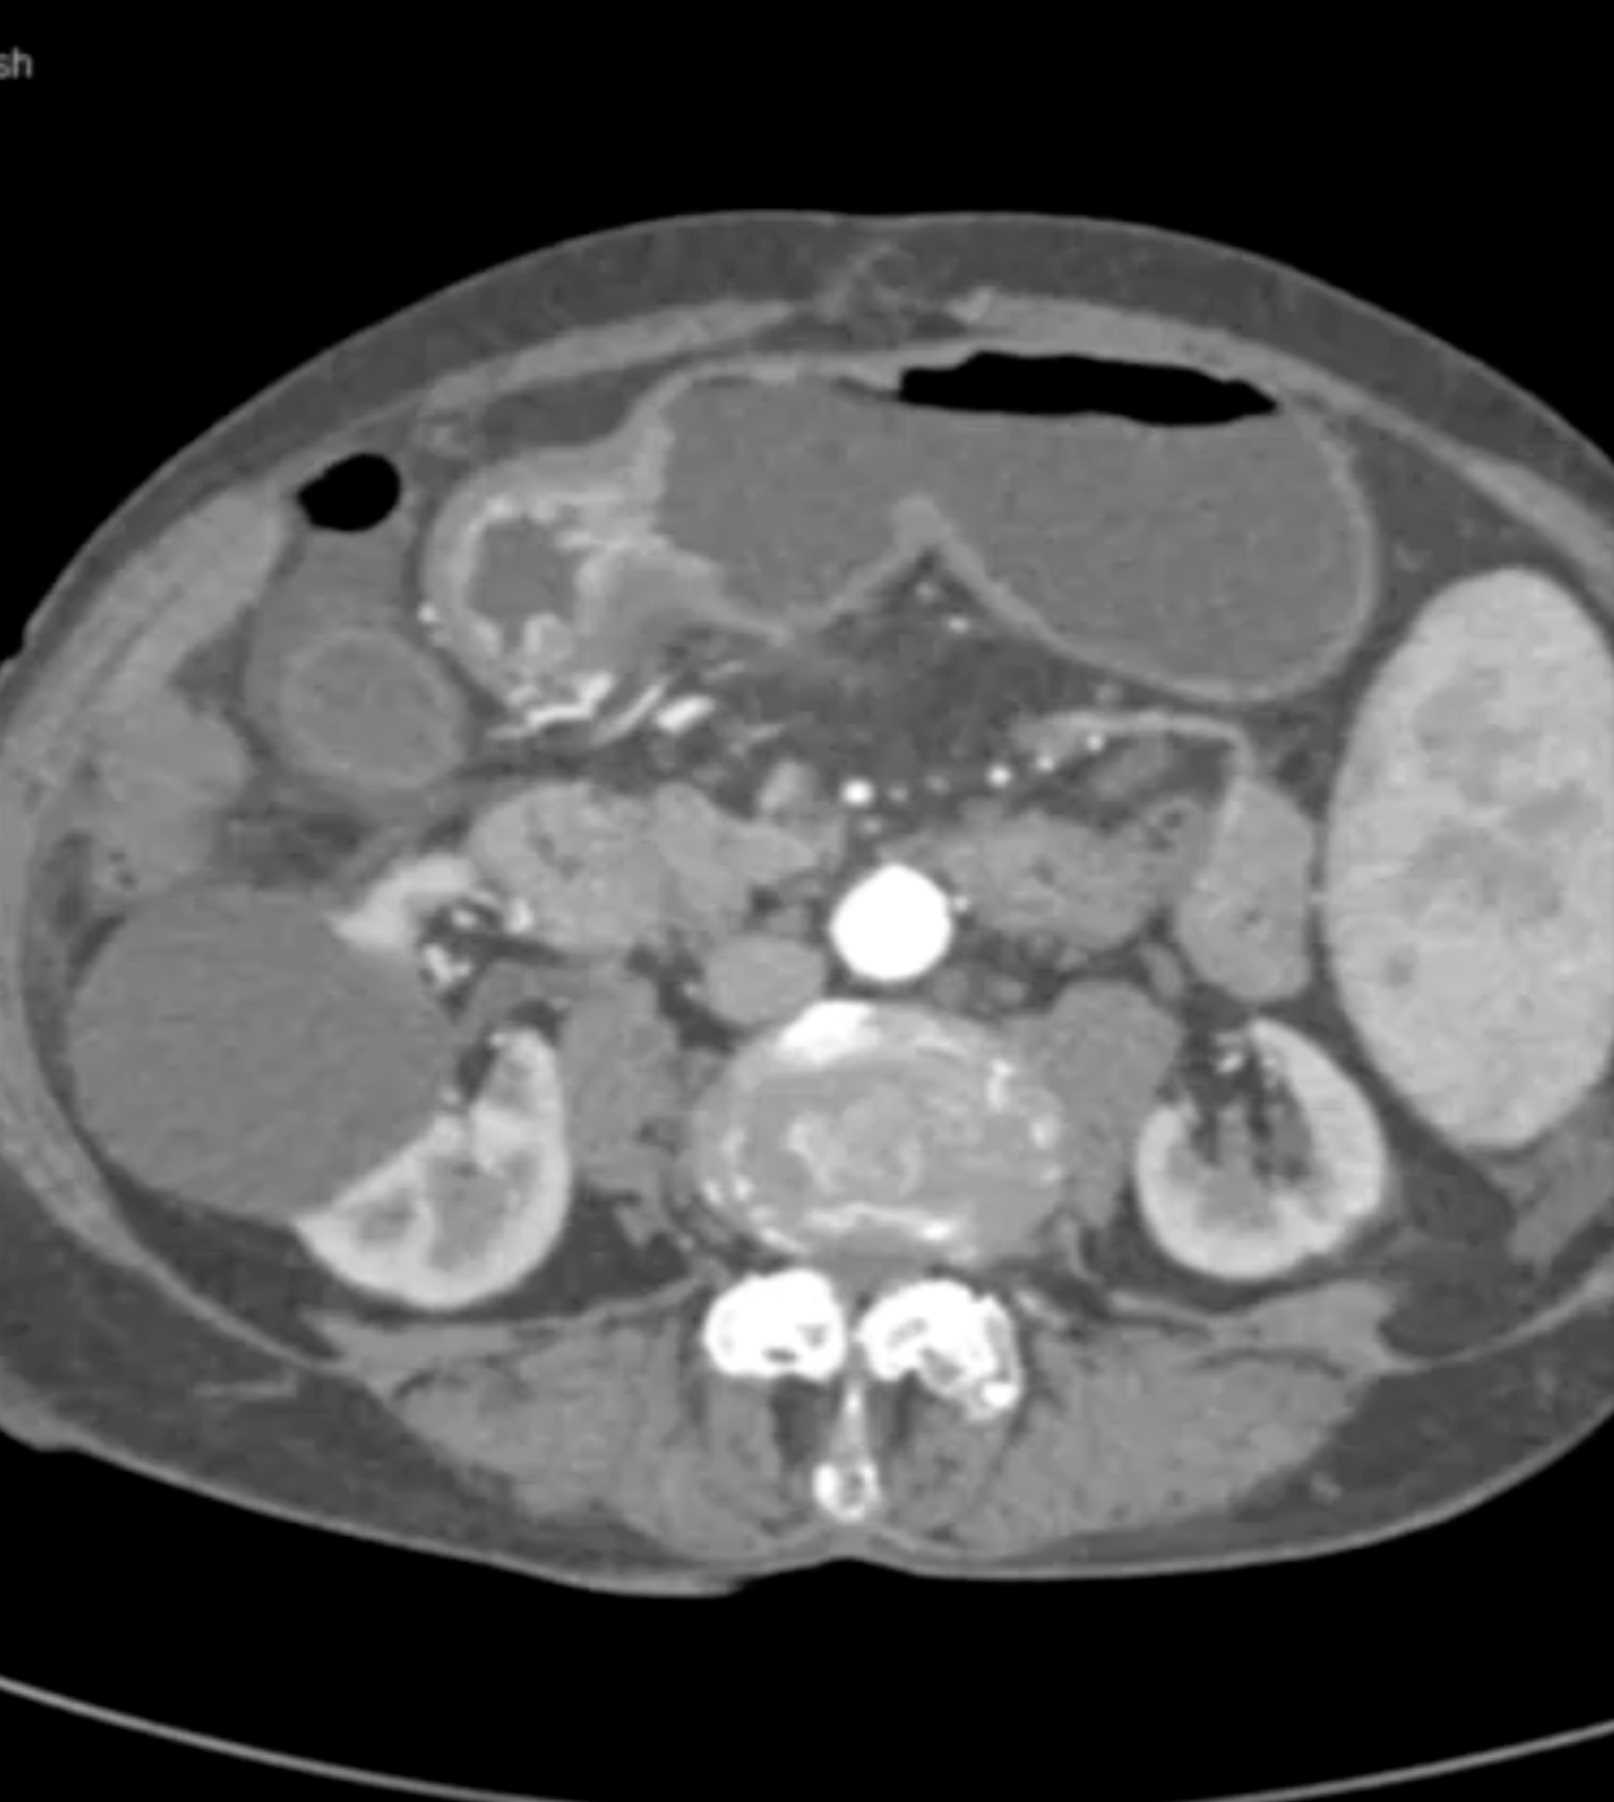

Lagre Gastric GIST Tumor